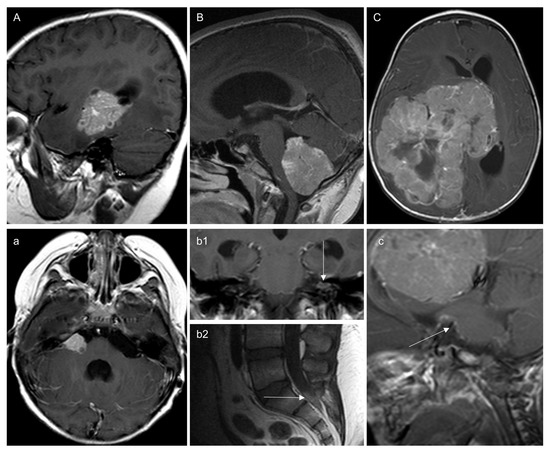

3.3. Leptomeningeal Dissemination (Table 2)

3.3.1. At Diagnosis

3.3.2. On Follow-Up